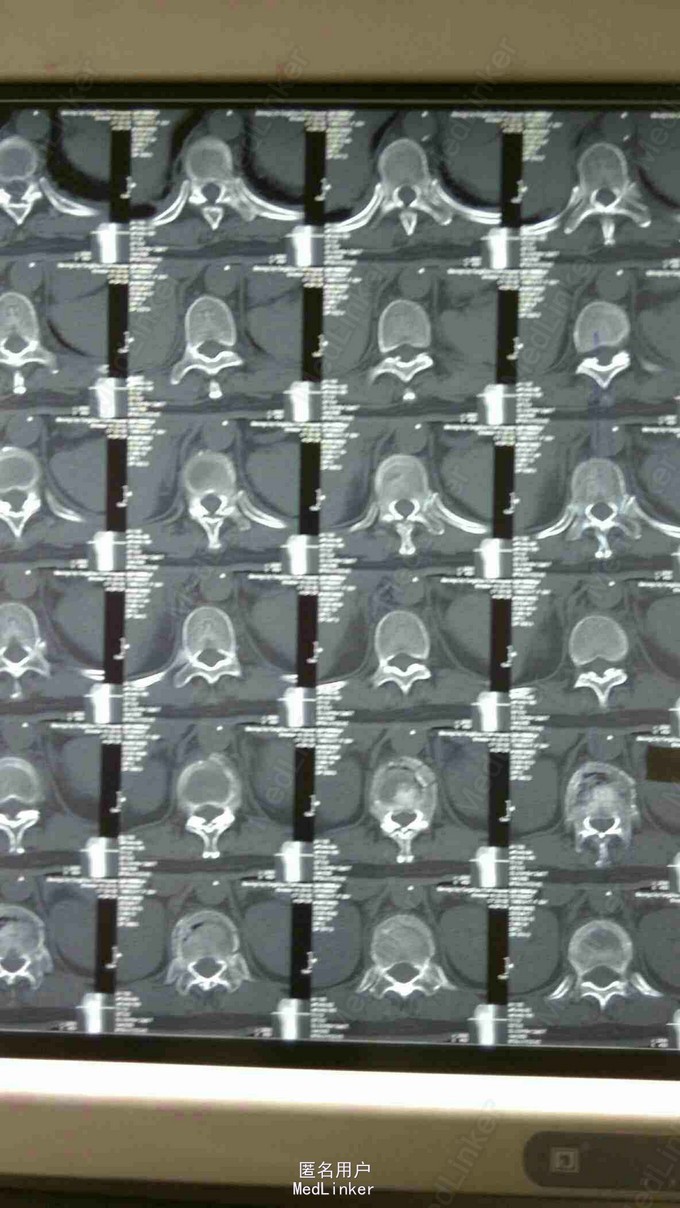

胸椎压缩骨折

患者,女性,55岁,主因外伤致胸背部疼痛3天入院

胸背部压痛及叩痛阳性,双下肢感觉运动血运良好。

胸11,12压缩骨折,行胸11,12pkp治疗后,患者腰背部疼痛明显缓解。